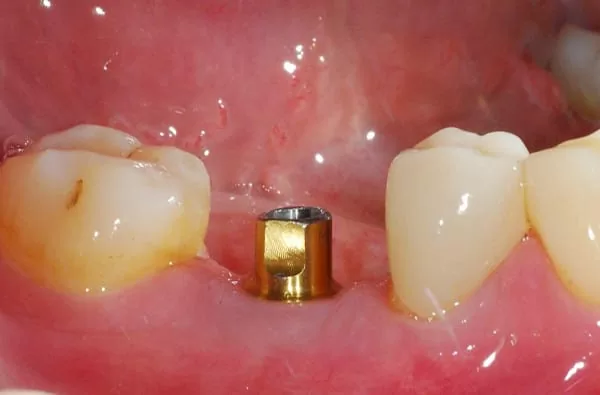

所以等約四個月後植牙,再等待三個月以新科技的植牙穩定度測量儀測量骨整合程度,發現骨整合情況良好,隨即以"臨時牙套"進行牙齦塑型,再製作全瓷冠恢復我的咀嚼功能。

經牙嵴保存術後再植牙,醫師說:這就是"植牙癒合帽"周圍牙嵴豐隆度很好~ (# ̄▽ ̄#)

細心的醫師先在石膏模型上模擬製作植牙全瓷冠給我看~